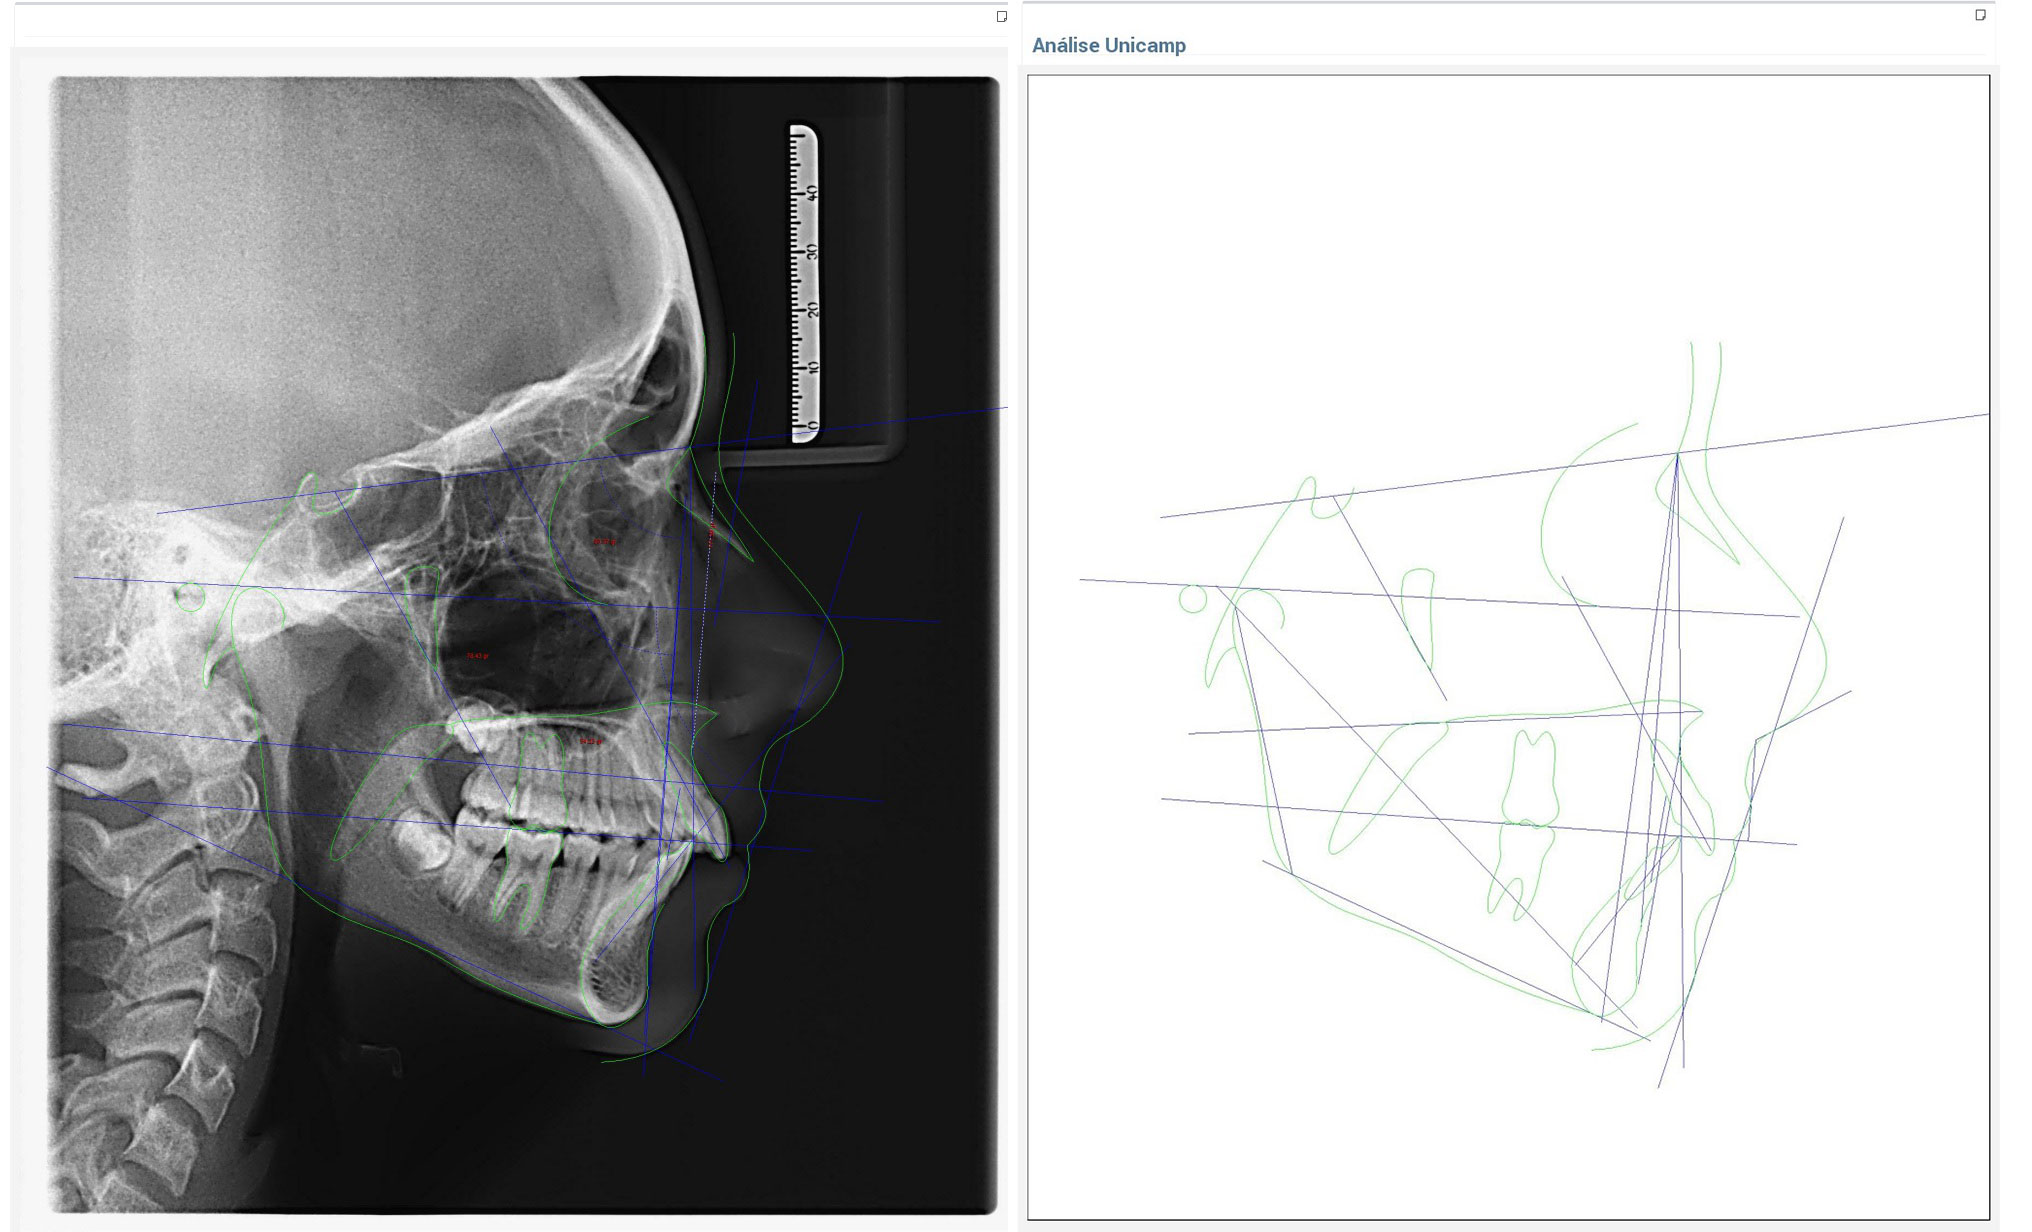

Radiografias Digitais

- Raio X Panorâmico

- Telerradiografia

Documentações